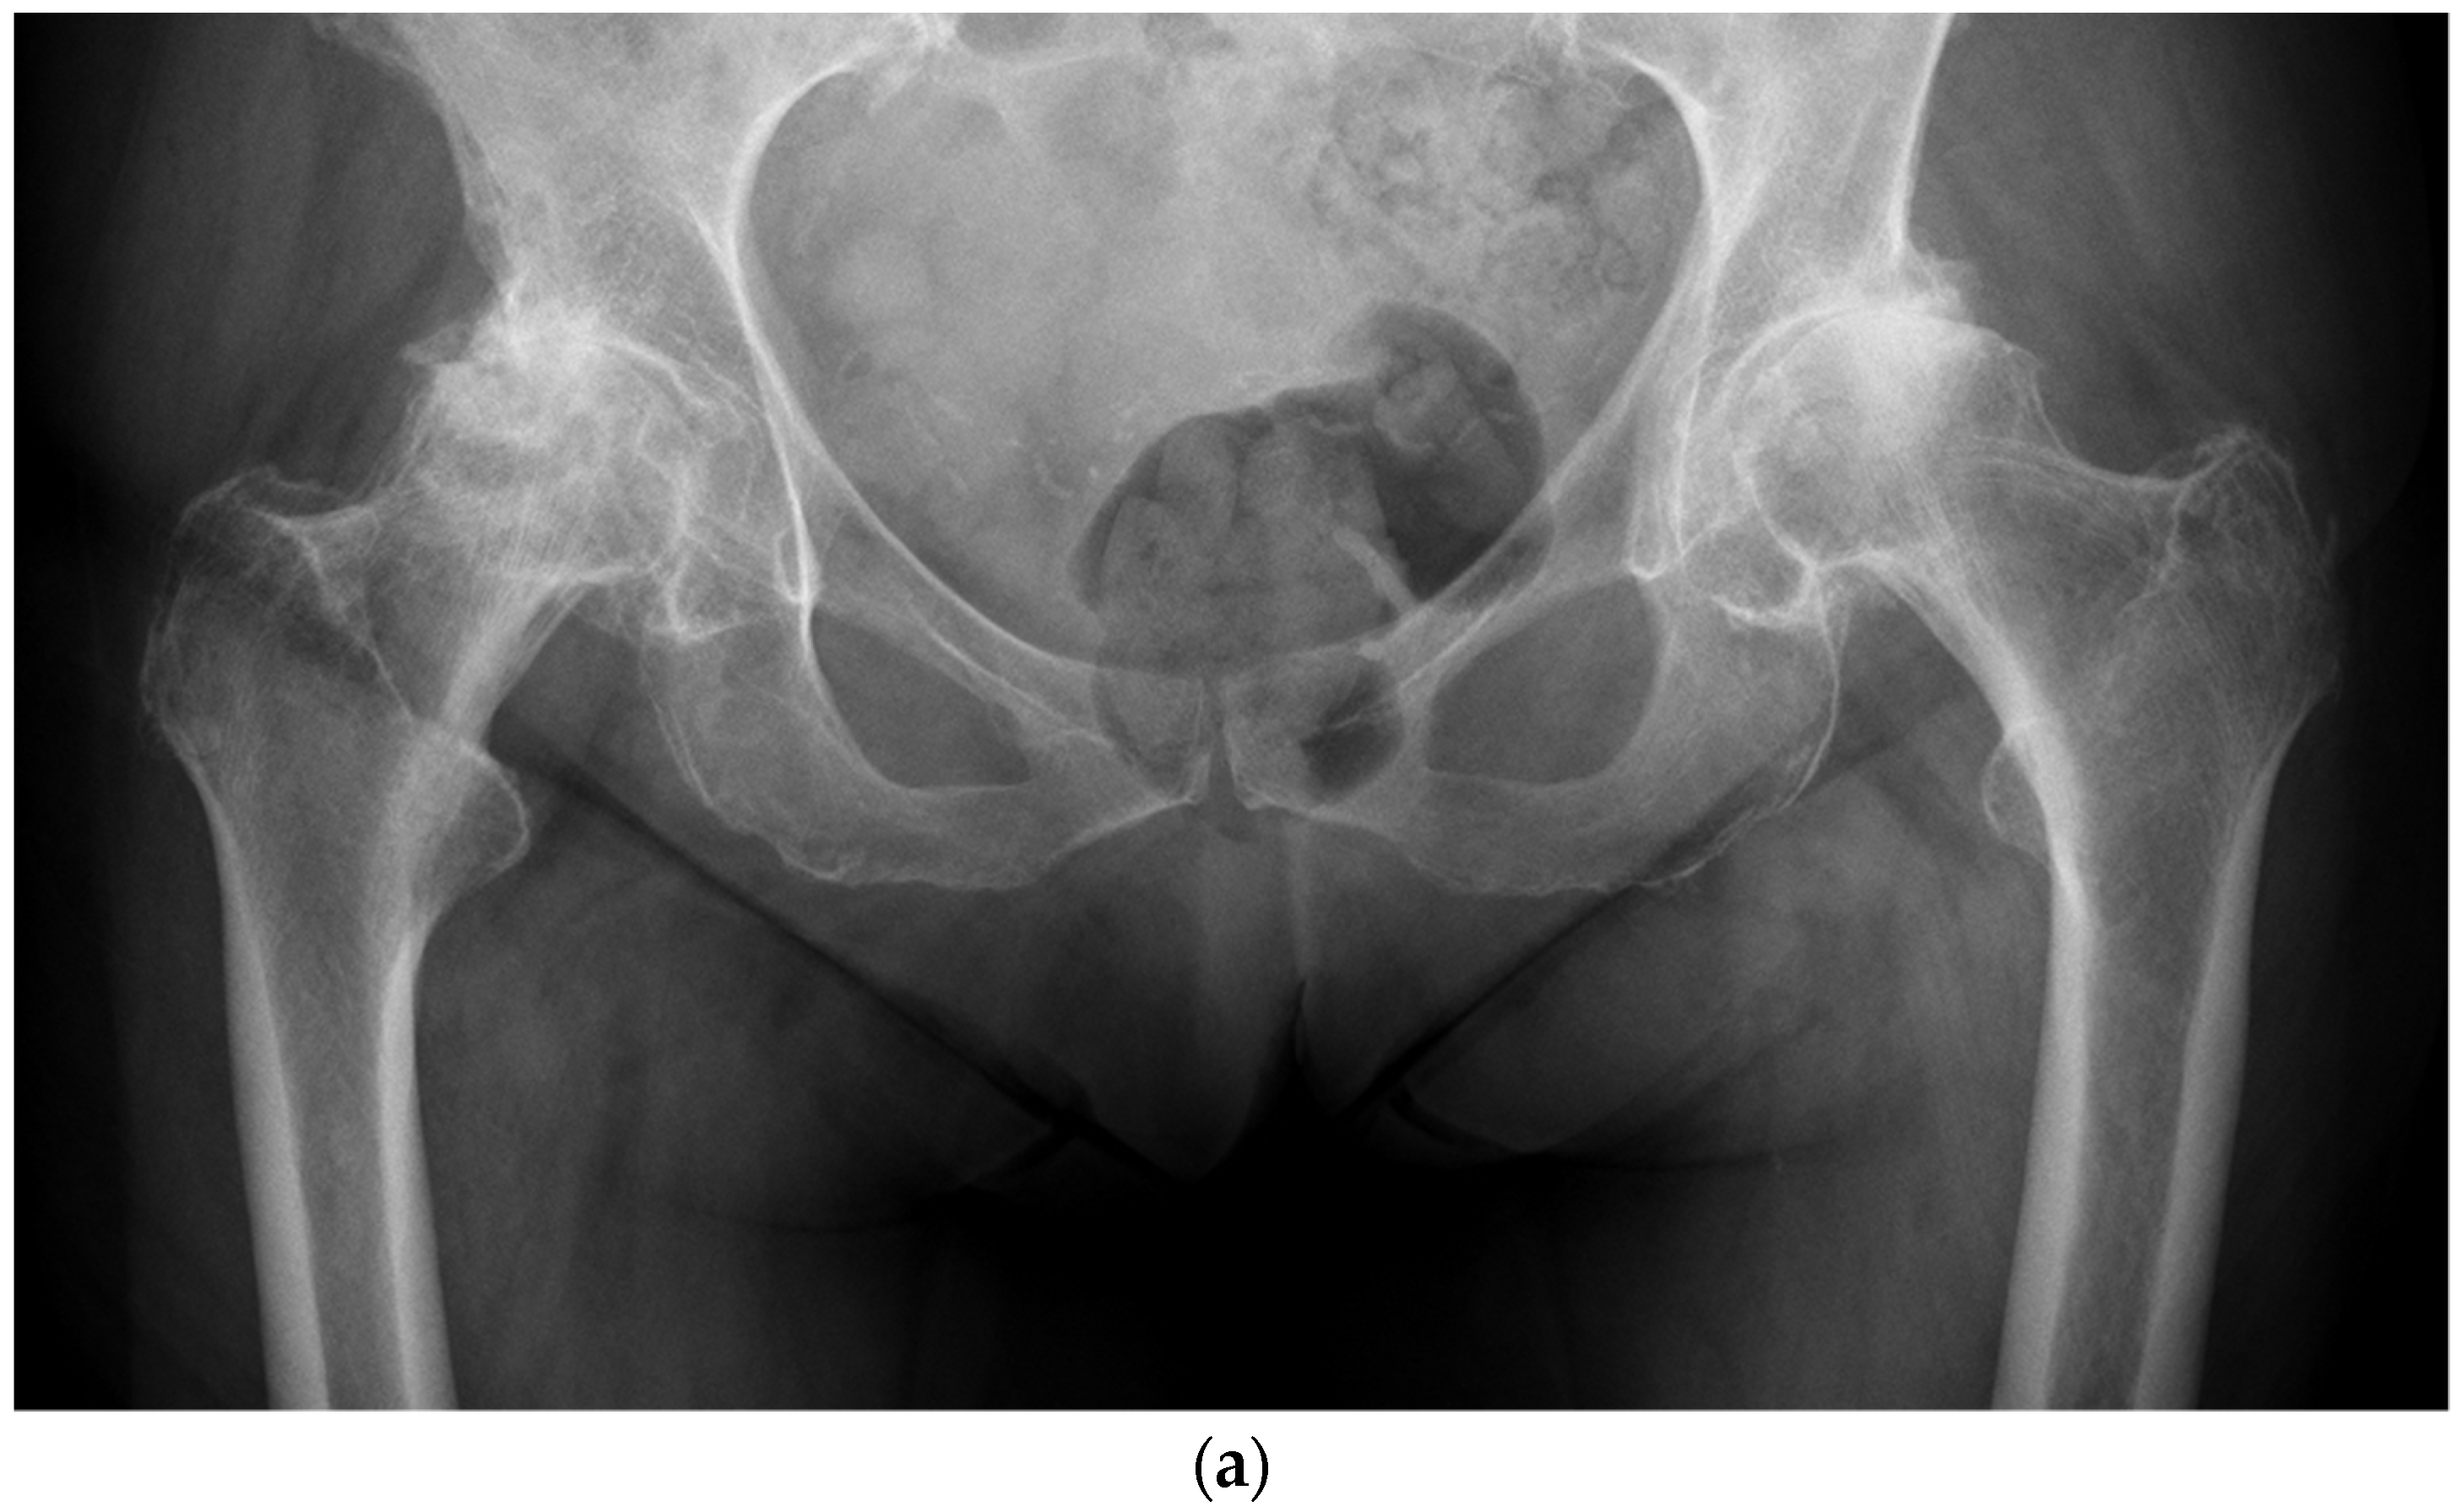

Figure 1.

(a) Anteroposterior pelvis radiograph of 19-year-old men with right femoral head avascular necrosis following a slipped capital femoral epiphysis treated with canulated screws. During preoperative templating, acetabular, and femoral components sizes were estimated to be small. (b) Preoperative lateral view of the right hip. (c) Postoperative anteroposterior pelvis radiograph showing a CoC LDH THA with a 13 mm conical stem and a 46 mm monobloc ceramic acetabular component with a bearing diameter of 36 mm. (d) Postoperative lateral view of the right hip replacement.